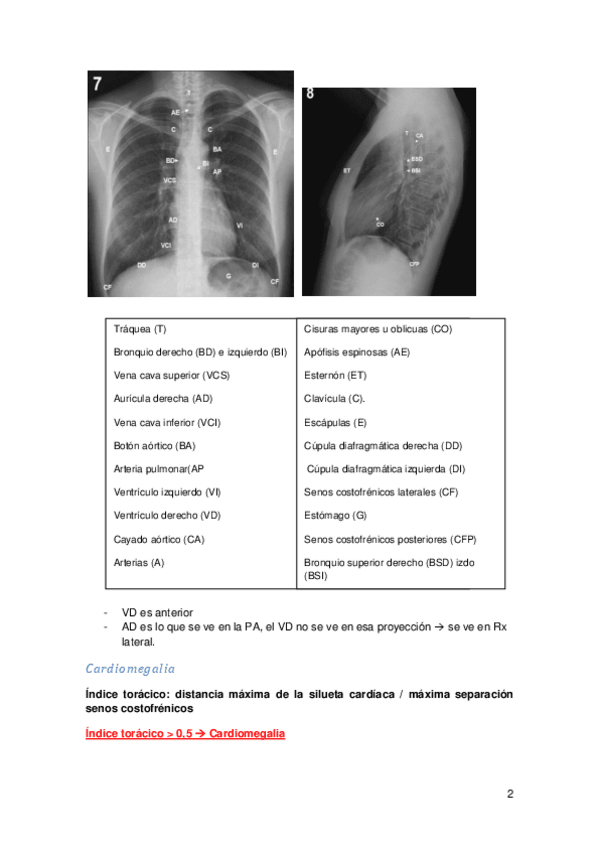

He publicado nuevos apuntes de 1º Apuntes Variados: Tema 20. Métodos diagnósticos en cardiología.pdf